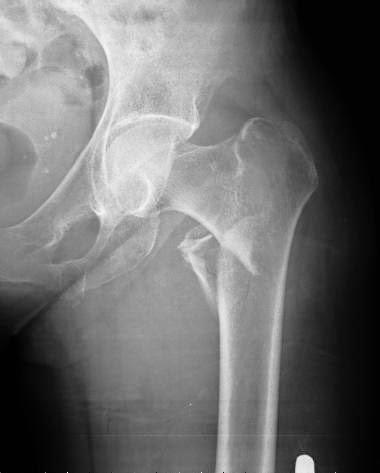

En este estudio argentino, la mitad de las densitometrías se pidieron en mujeres que no cumplían los criterios recomendados de edad o de riesgo aumentado para justificar el rastreo de osteoporosis. Salud Colectiva, octubre de 2016

Una revisión sistemática de los umbrales de intervención basados en la herramienta FRAX para la estimación del riesgo de fractura. Archives of Osteoporosis, 27 de julio de 2016